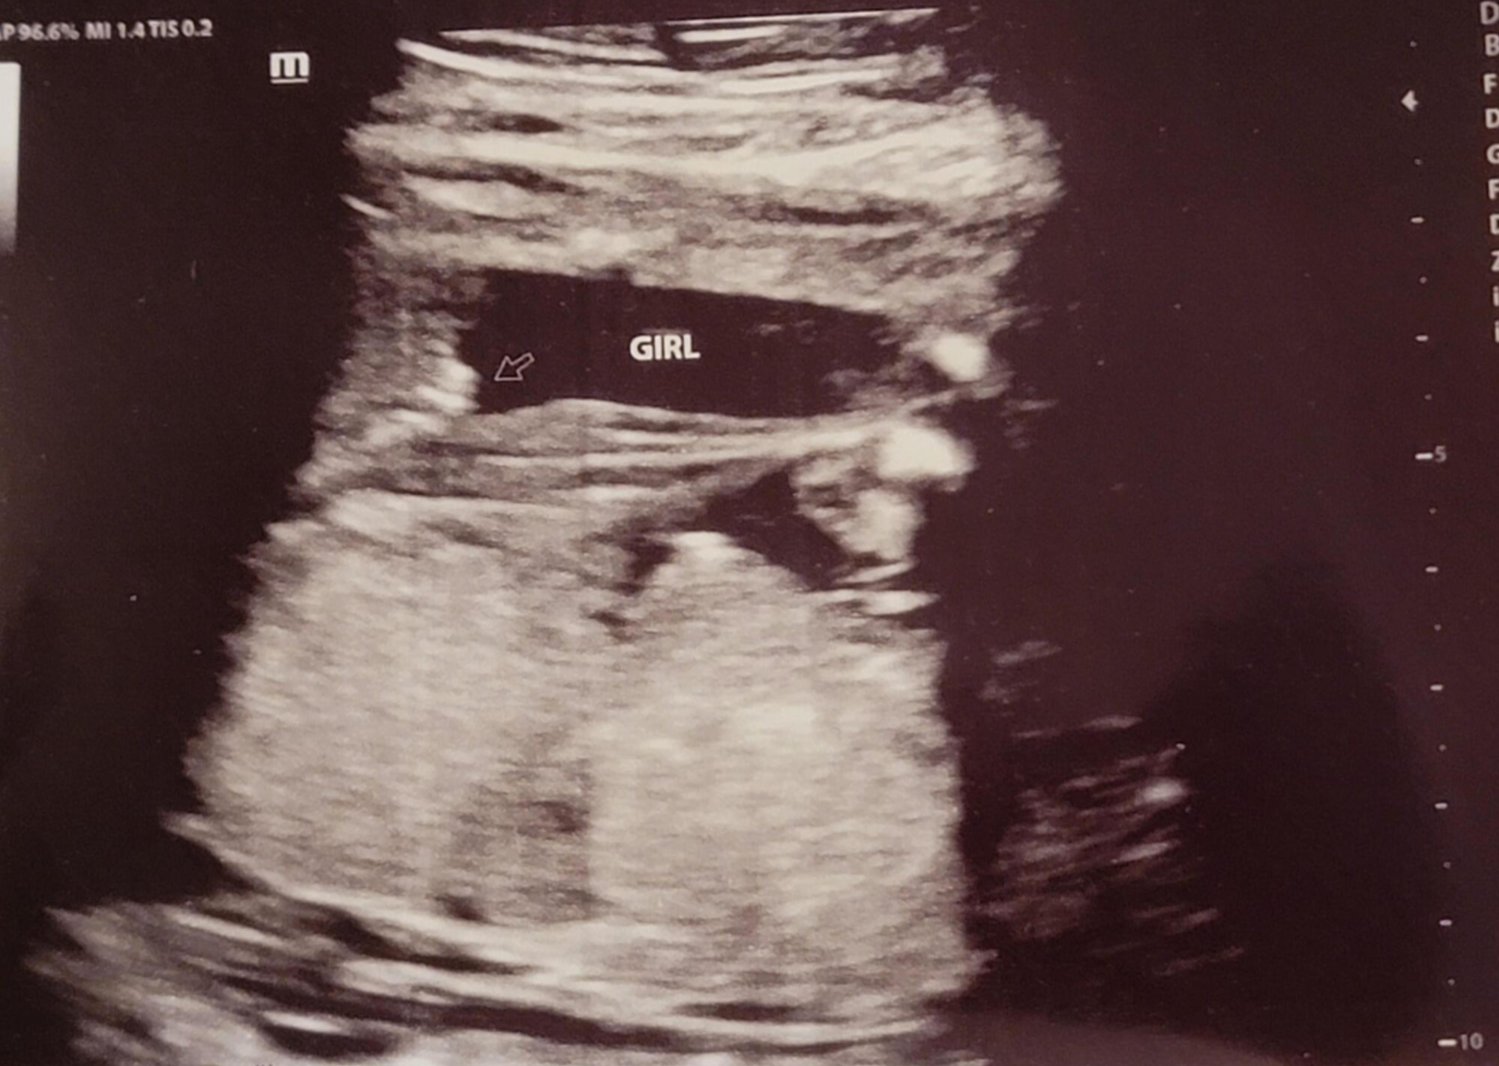

임신 20주 정밀 초음파 검사 : 성별 반전

20주 정밀초음파를 받았는데 아이 건강상태를 꼼꼼하게 확인하고 마지막으로 성별을 확인했는데 딸이라고... 저에게 성별 반전이 있었어요~ 그래서 믿을 수가 없어서 제가 초음파 검사를 했을 때마다 아들이라고 했는데 지금 딸이라 해서 너무 혼란스럽다고 하니 다시 누워보라며 다시 봐주셨는데 역시나 딸 ^^~ 확실한 성별 반전! 딸을 더 원했던 남편은 저의 기분을 생각하지 않고 너무 행복해하더라고요 ㅋㅋㅋㅋㅋ ;;

성별이 중요하진 않지만... 이미 받은 선물들도 있고 아들이라고 해서 좋아했던 가족들에게 너무 미안해서 혼자서 훌쩍훌쩍... 눈물을.....;;;; 그리고 감정을 추스르고 가족에게 전화를 해서 딸이라고 말을 하니 성별이 뭐가 중요하냐고 너무 이쁘겠다며 요즘은 딸이 최고라고 하면서 저의 기분을 달래주셔서 미안한 마음과 고마운 마음이 동시에 들었어요~!

위에 아들이라 했던 초음파 사진은 다 딸 초음파 사진이니 성별이 궁금하신 분들은 딸 초음파 사진으로 참고해서 보시면 좋을 것 같아요~그리고 전 결혼 5년 만에 가진 첫 아이라 설레는 마음에 너무 이르게 아이 용품들을 준비했는데 출산 2~3달 전에 준비해도 늦지 않은 것 같아요~ 혹시 저처럼 성별 반전이 있을 수 도 있으니 아이 용품은 천천히 준비하시길~~!